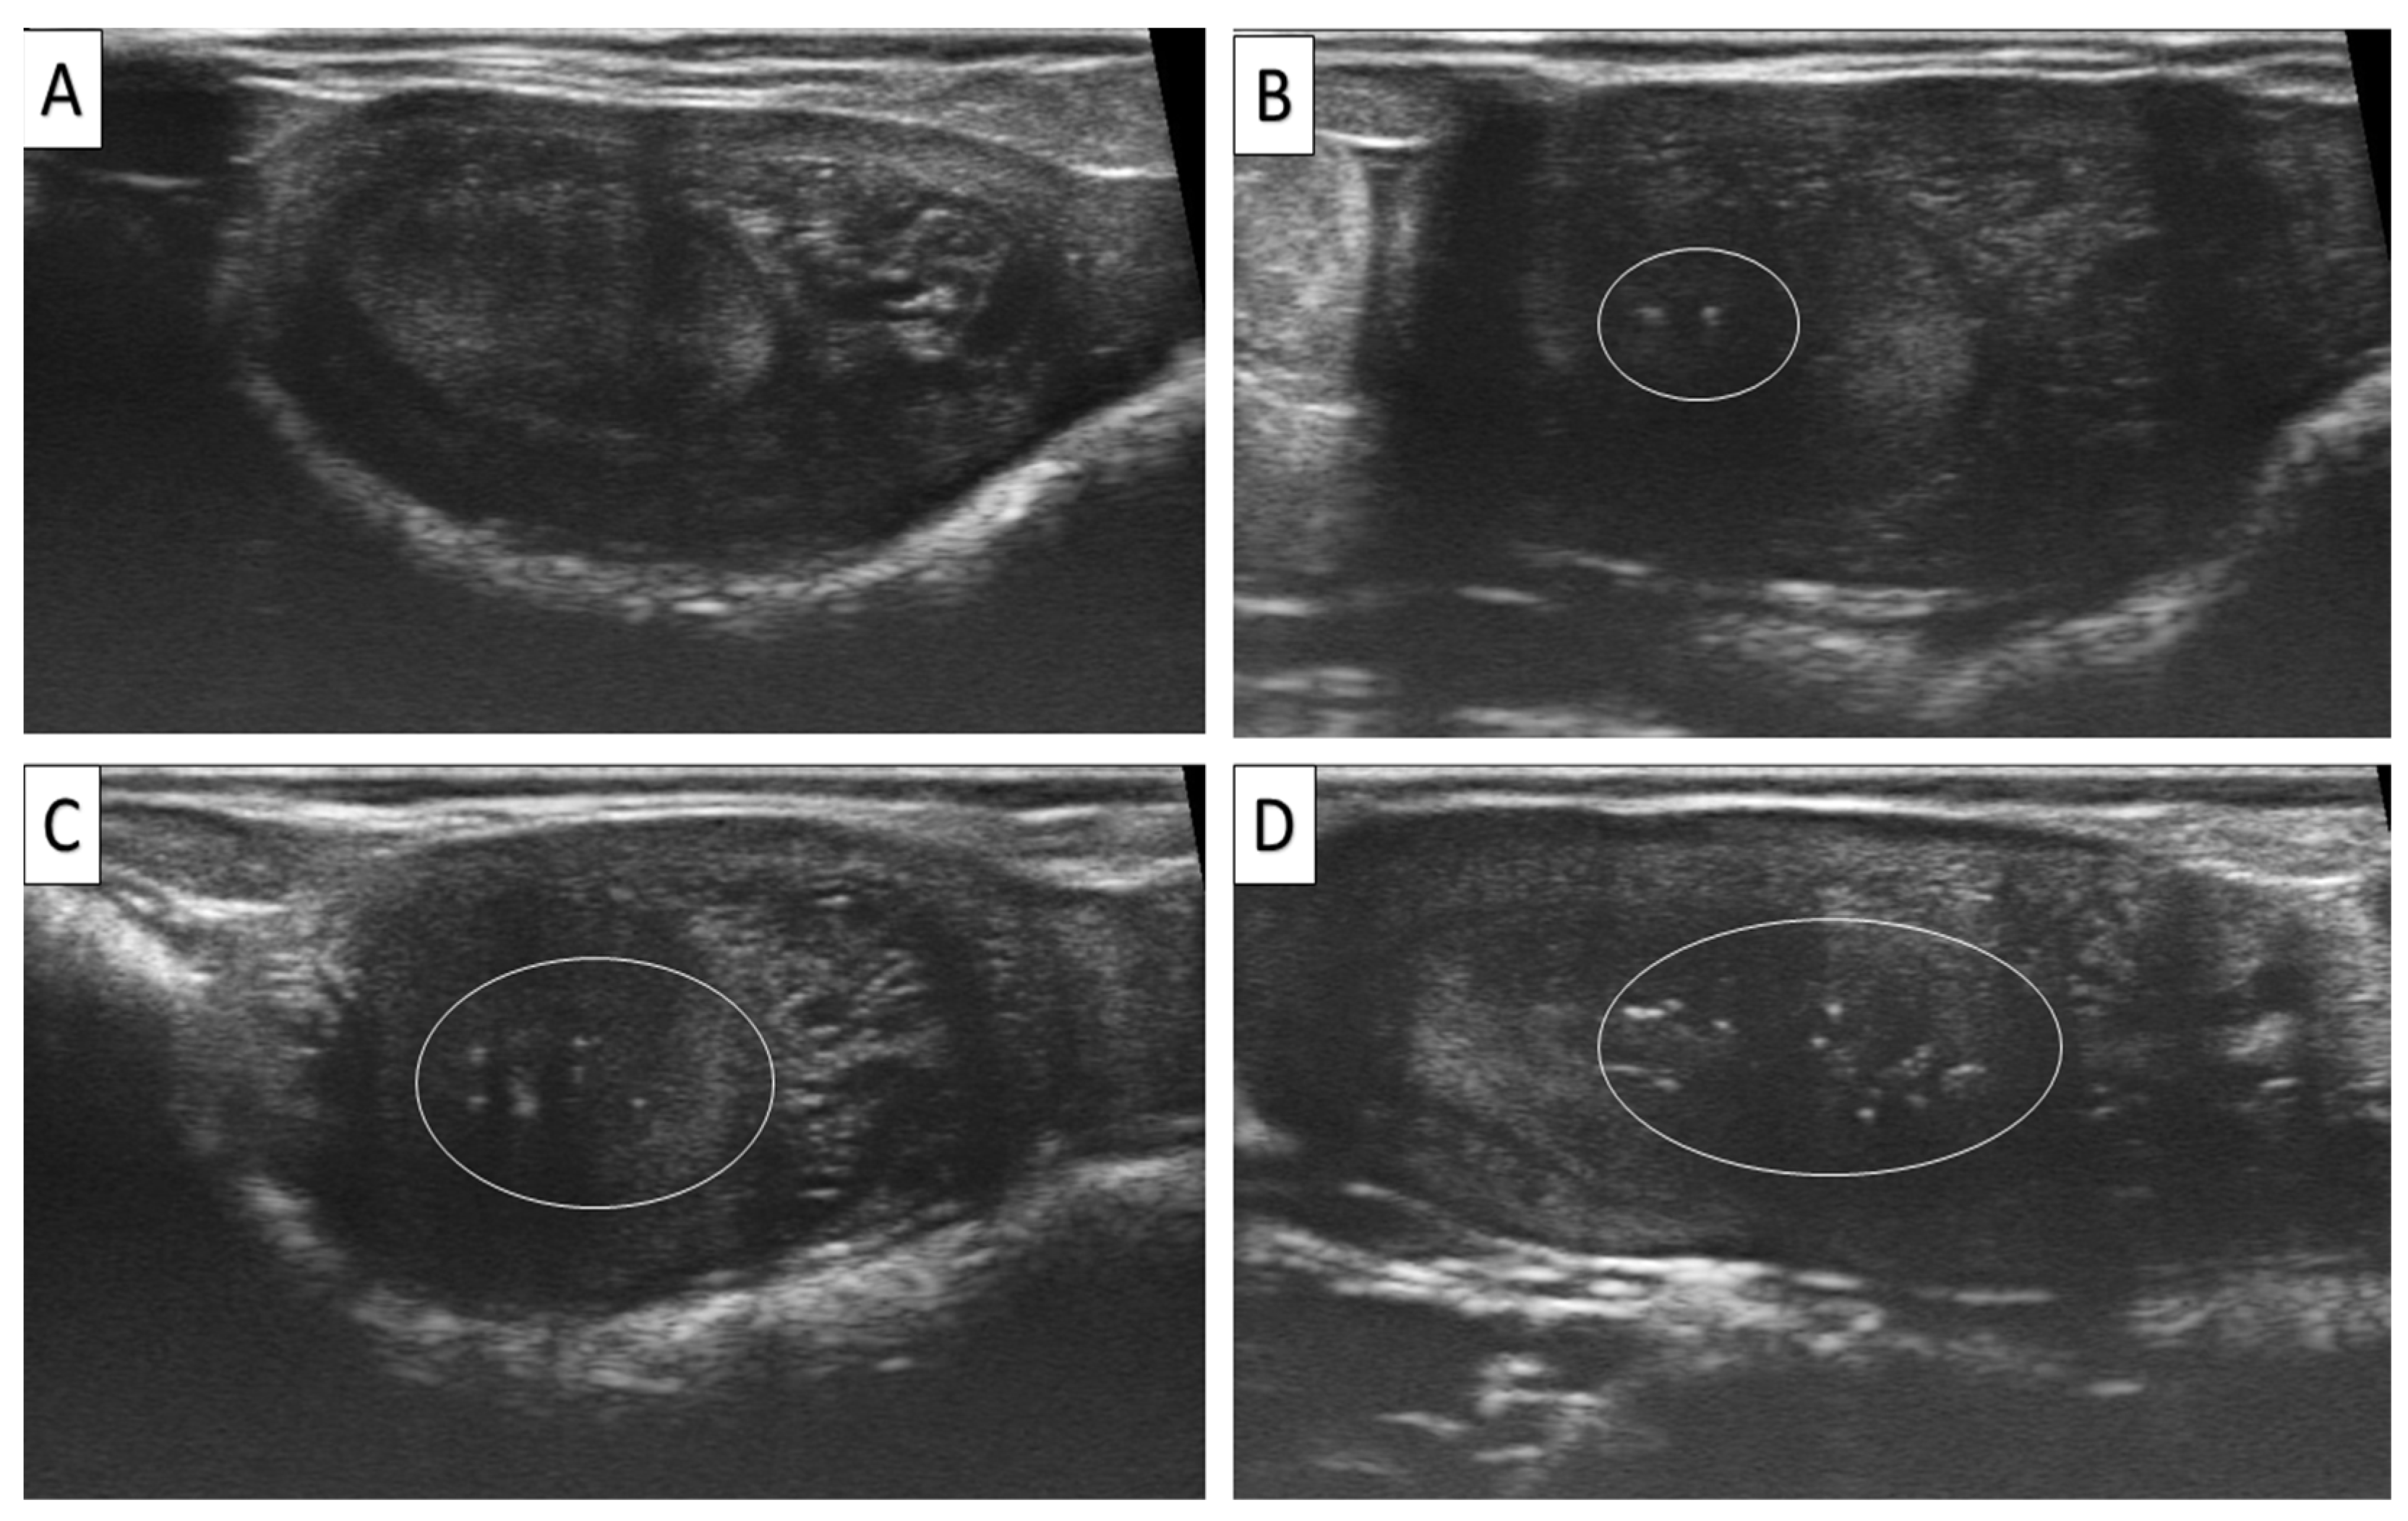

2.5. Assessment of EMs and Uterine Tone

3.1. Effect of Uterine Factors (EMs and Tone) on PR

| 2 | Endometrial Microcalcifications | Total | <0.01 | ||||

| Grade 0 | 2747 (63) | 847/2747 (30.83) | Indicator | ||||

| Grade 1 | 1533 (35.2) | 390/1533 (25.44) | 0.667–0.885 | 0.768 | <0.01 | ||

| Grade 2 | 80 (1.8) | 20/80 (25.00) | 0.449–1.255 | 0.751 | <0.05 | ||